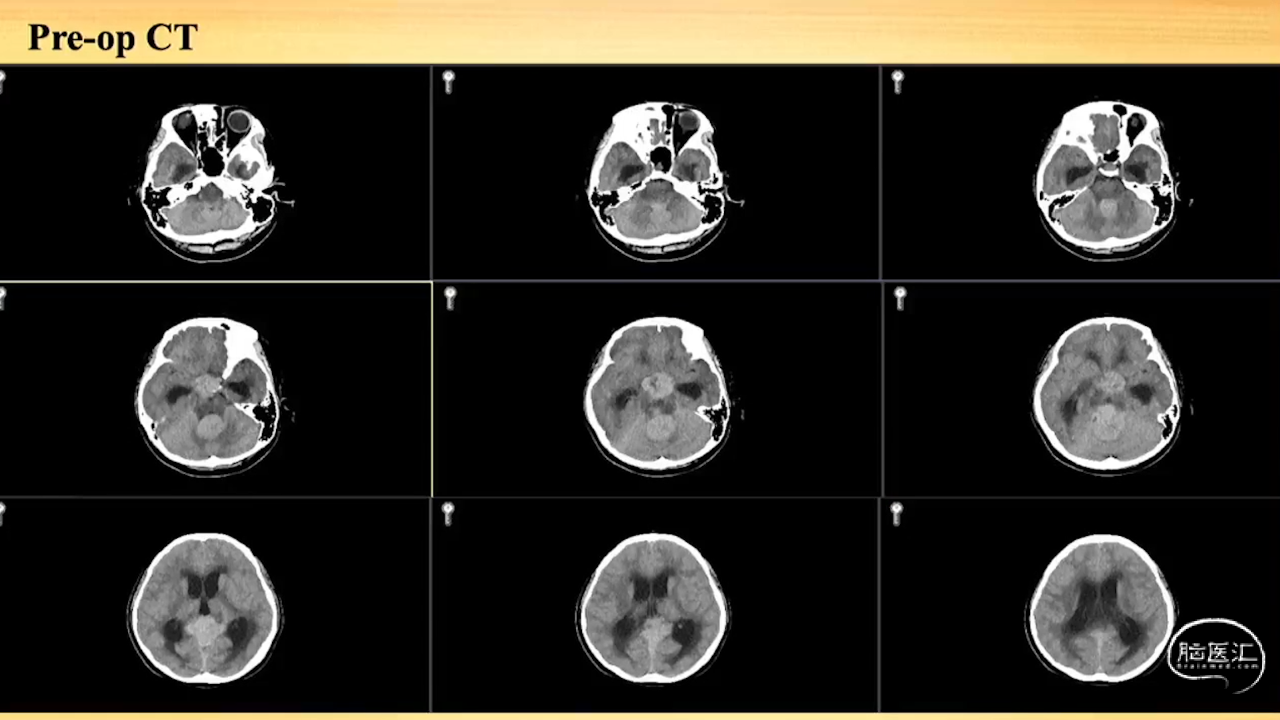

张荣教授:儿童颅内生殖细胞瘤的手术治疗

颅内生殖细胞肿瘤的治疗是手术、放疗、化疗、内分泌及其他多学科的整合治疗。及时、精准、合理的手术治疗是iGCT患者提高生存率、降低并发症、改善神经内分泌功能的关键。